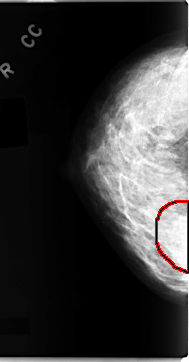

C_0098_1.RIGHT_MLO

RIGHT_CC LINES 4704 PIXELS_PER_LINE 2456 BITS_PER_PIXEL 12 RESOLUTION 50 OVERLAY

FILE: C_0098_1.RIGHT_CC.OVERLAY

TOTAL_ABNORMALITIES 1

ABNORMALITY 1

LESION_TYPE MASS SHAPE IRREGULAR MARGINS ILL_DEFINED

ASSESSMENT 4

SUBTLETY 3

PATHOLOGY MALIGNANT

TOTAL_OUTLINES 1

BOUNDARY